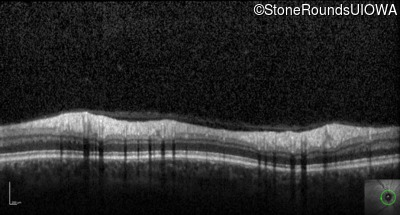

Optical Coherence Tomography - Right - 20/400 sc

Exemplar / OCT Stack